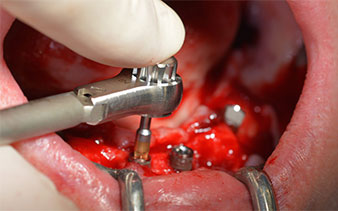

Das chirurgische Protokoll der verwendeten Implantate (SKY, bredent medical) schreibt eine Umdrehungszahl von 1.200/min für die Pilotbohrungen vor (Abb. 7–9).

Umdrehungszahl von 1.200/min

Abb. 8

Abb. 9

Dies entspricht der nächsten Position der Voreinstellung am Implantmed. Zu erkennen ist die etwa 45-Grad-Schräghaltung des W&H Winkelstückes nach mesiokaudal in Regio 45, um den Nervus mentalis zu schonen. Das Foramen mentale gilt als anatomische Orientierung für alle Bohrungen in diesem Bereich. Die anschließenden Bohrungen werden mit einer reduzierten Umdrehungszahl von 300/min durchgeführt (Abb. 10 und 11).